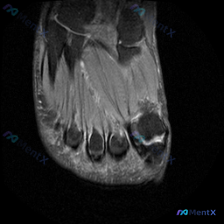

看到一个很有代表性的影像读片病例,整理了完整分析思路分享给大家。 病例基本信息 本次提供的是单张足踝部MRI T1序列矢状位影像,临床怀疑存在「软骨异常」,要求进行影像学解读分析。 影像基础评估 先给大家整理一下这张影像的基础观察结果: 1. 骨骼结构:胫骨远端、距骨、跟骨、舟骨等骨骼形态轮廓清晰,...